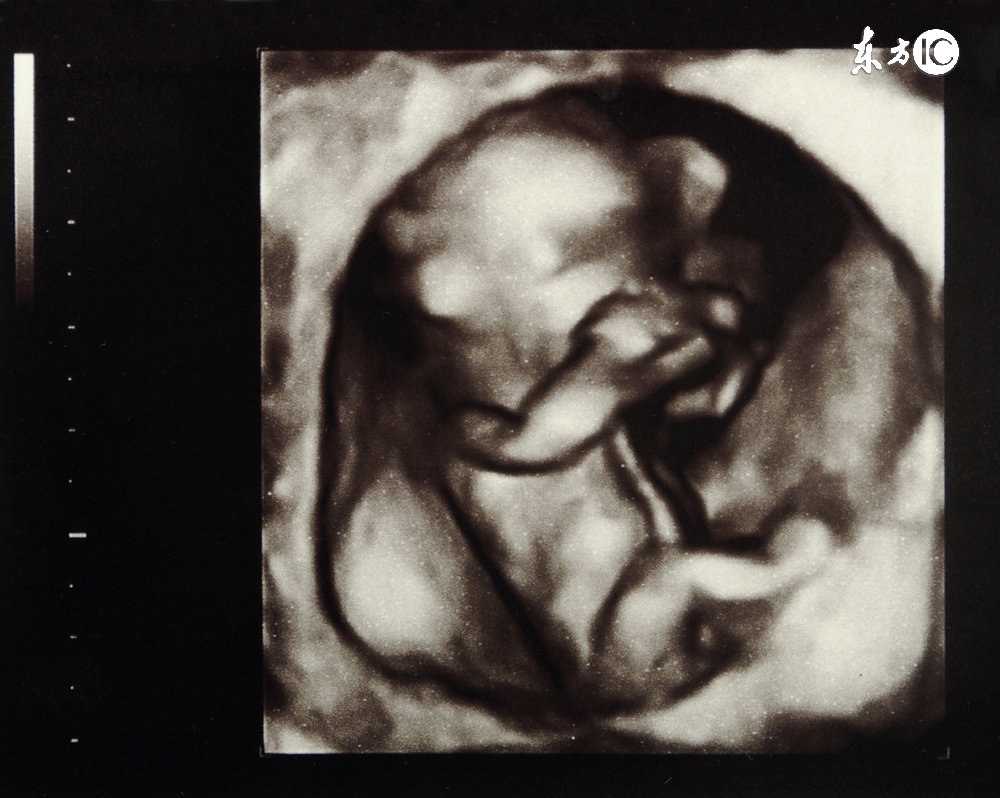

十月怀胎,终于到了瓜熟蒂落的时候了,是不是很令人兴奋呢?可是37-39周腹中的胎儿生长发育是否正常呢?各项数据的正常值美妈们都知道吗?来看看这些!

10个月胎儿的各个器官已经发育成熟,他的小手和小脚的肌肉都长好了呢,骨骼也变硬了,长出了3~4厘米的头发。而肺部是最后一个成熟的器官,在宝宝出生后几个小时内他才能建立起正常的呼吸模式。

在第37周时,胎儿就已经会自动转向光源,可对妈妈身体内外的各种刺激做出反应,敏锐地感知妈妈的思考和心情、情绪,所以这个时候你一定要保持愉悦的心情来迎接他哦!

孕10月产检:

临近预产期,这个月的产检以常规检查和胎心监护为主,准妈妈养成每天自行检测胎动的习惯。

检查时间:怀孕37周(第10次产检)、怀孕38周(第11次产检)、怀孕39周(第12次产检)、怀孕40周(第13次产检),怀孕10个月,孕晚期。

产检项目:血压、体重、宫底高度、腹围、胎心率、血常规、尿常规、胎心监护、胎位检查、骨盆测量(怀孕37周)、宫颈检查(Bishop评分)(怀孕39周)。